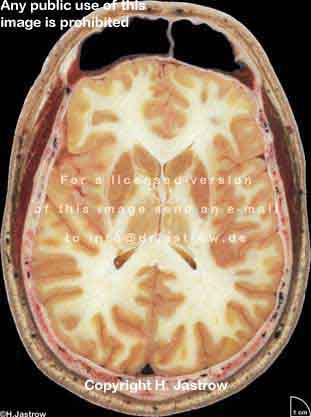

??? ! § ! Copyright H. Jastrow

Visible Human male: Sectio transversalis 1084

NMR

Pd T1 T2